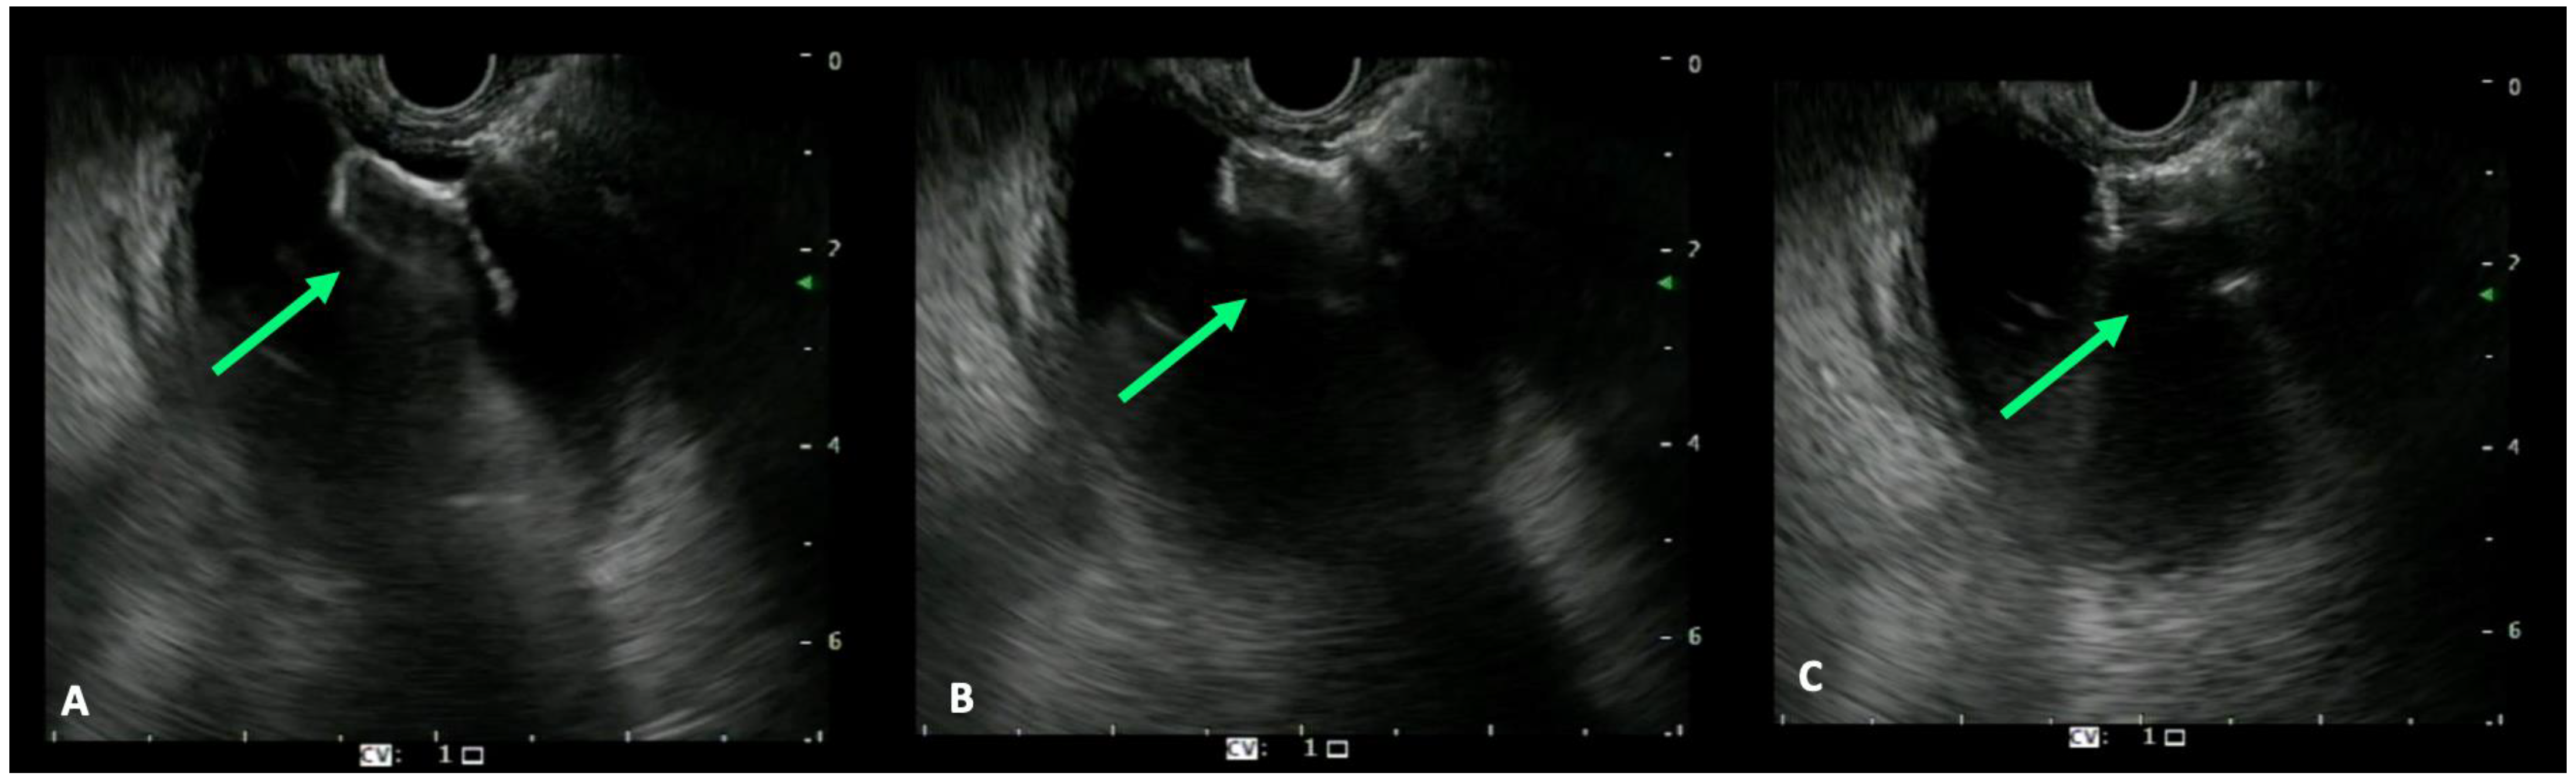

- Mangiavillano, B.; Moon, J.H.; Crinò, S.F.; Larghi, A.; Pham, K.D.; Teoh, A.Y.B.; Paduano, D.; Lee, Y.N.; Yoo, H.W.; Shin, I.S.; et al. Safety and efficacy of a novel electrocautery-enhanced lumen-apposing metal stent in interventional EUS procedures (with video). Gastrointest. Endosc. 2022, 95, 115–122. [Google Scholar] [CrossRef] [PubMed]

- Ogura, T.; Itoi, T. Technical tips and recent development of endoscopic ultrasound-guided choledochoduodenostomy. DEN Open 2021, 1, e8. [Google Scholar] [CrossRef]

- Ogura, T.; Higuchi, K. Technical tips of endoscopic ultrasound-guided choledochoduodenostomy. World J. Gastroenterol. 2015, 21, 820–828. [Google Scholar] [CrossRef]